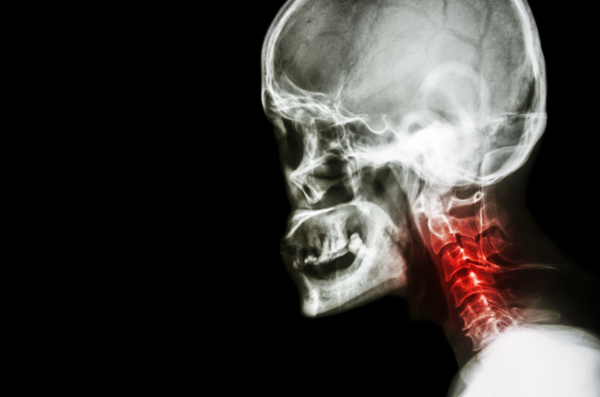

郎平指导提到的“颈椎置换”,医学上称为颈椎人工椎间盘置换术。它并非更换整节颈椎骨,而是通过植入一个可活动的人工椎间盘,来替代已经病变的颈椎间盘。

颈椎人工间盘置换术,主要用于治疗因颈椎间盘突出或颈椎管狭窄导致的神经压迫,其核心目标是在解除神经压迫的同时,最大程度保留颈椎的活动功能。这项技术最早于2000年前后在欧美获批应用,国内2003年左右引入,迄今已有超过20年的临床实践,在部分三甲医院和专科医院脊柱外科开展。

需要注意的是,术前需经系统评估,首先通过临床查体了解颈椎活动度,进而结合影像学检查综合判断:X光片用于观察颈椎整体序列与动态活动度;CT扫描能清晰呈现骨质结构与增生情况;而核磁共振可以精确评估椎间盘的退变与神经受压程度。最终,是否适合手术,须由经验丰富的脊柱外科医生基于详尽的临床与影像学评估来审慎决定。